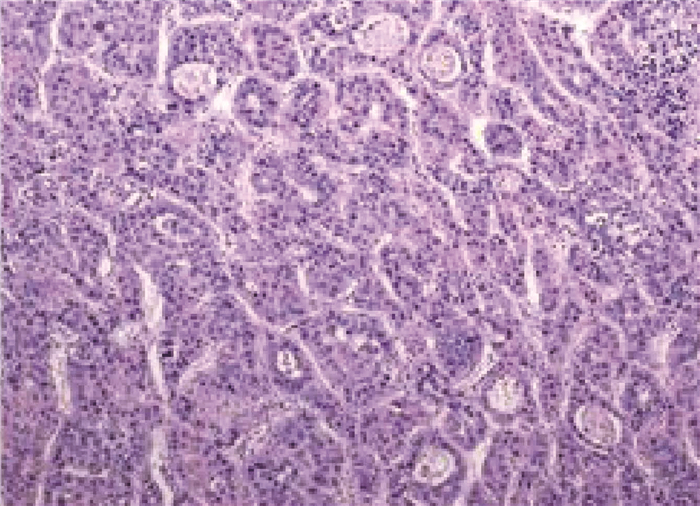

Complete remission after comprehensive treatment of lung metastases following liver cancer surgery: A case report